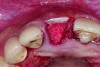

In cases with an incomplete facial plate, the ice cone technique was recommended.20 In this method, a collagen membrane was trimmed to the shape of an ice cone and placed into the socket against the inner aspect of the facial bone. The socket was filled with bone substitutes, and the coronal portion of the membrane was used to cover and protect the underlying bone substitutes. A non-resorbable PTFE membrane can be used for site preservation as well.21 This membrane, if secured to bone, can be left exposed, and epithelialization will occur over it. It was found that sockets grafted with a mineralized bone allograft and PTFE membrane had 47.4% new bone formation and 14.7% residual graft particles. In addition, there was minimum resorption of the buccal bone thickness, as indicated by a 0.3-mm horizontal bone resorption and a 0.25-mm vertical bone resorption.22 A recent systematic review reported that the use of PTFE membranes in ridge preservation shows potential in maintaining ridge dimensions23 and possibly aiding in increasing the zone of keratinized mucosa. Therefore, the use of PTFE membrane may be preferred in ridge preservation of sites in the esthetic zone. Figure 1 and Figure 2 illustrate the use of PTFE membrane in ridge preservation for implant replacement in the esthetic zone. Other authors have also attempted primary closure of the socket or to improve the ridge topography with soft-tissue grafts, but it has not been proven to be effective in increasing bone regeneration.18

In sites with an intact and thick (≥2 mm) buccal bone, no grafting is required. A collagen plug may be used for hemostasis at the site of extraction. In sites with an intact and thin (<2 mm) buccal bone, the mineralized bone allograft-plug augmentation technique is preferred because of its effectiveness. For sites with no or incomplete buccal bone, the PTFE membrane can be placed between the bone and buccal soft tissue to form the buccal border. It is subsequently folded over the entrance of the socket, thus serving to contain and protect the bone graft that is placed into the socket. The PTFE membrane is removed 4 weeks after placement,23 and soft tissue will granulate over the site, thus increasing the soft-tissue thickness, which is beneficial for an esthetic implant restoration. Simultaneous or staged GBR, onlay grafts, ridge expansion, or distraction osteogenesis may be used to further augment the residual ridge if necessary. Soft-tissue augmentation can be performed before ridge augmentation or at implant uncovering stage, depending on the soft tissue thickness and width of keratinized mucosa.

Placement of PTFE membrane to form the missing buccal bone.

Figure 1